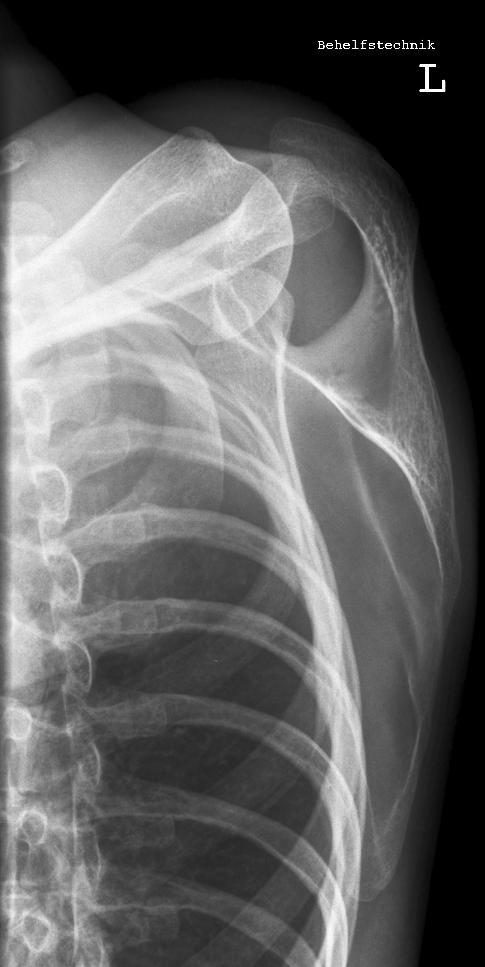

Schulter seitlich

SchulterY.jpg

Fehler

Bei dieser Aufnahme wurde der Patient zu weit gedreht, dass somit der Oberarm in den Rippen verschwunden ist. Zudem scheint der Patient einen Buckel gemacht zu haben.

Abhilfe

Abhilfe bringt erstens den Patienten aufrechter hinzusetzen; den Arm richtig lagern, sprich Hand auf dem Bauch und zweitens auf die Drehung von 45° beim Patienten zu achten.